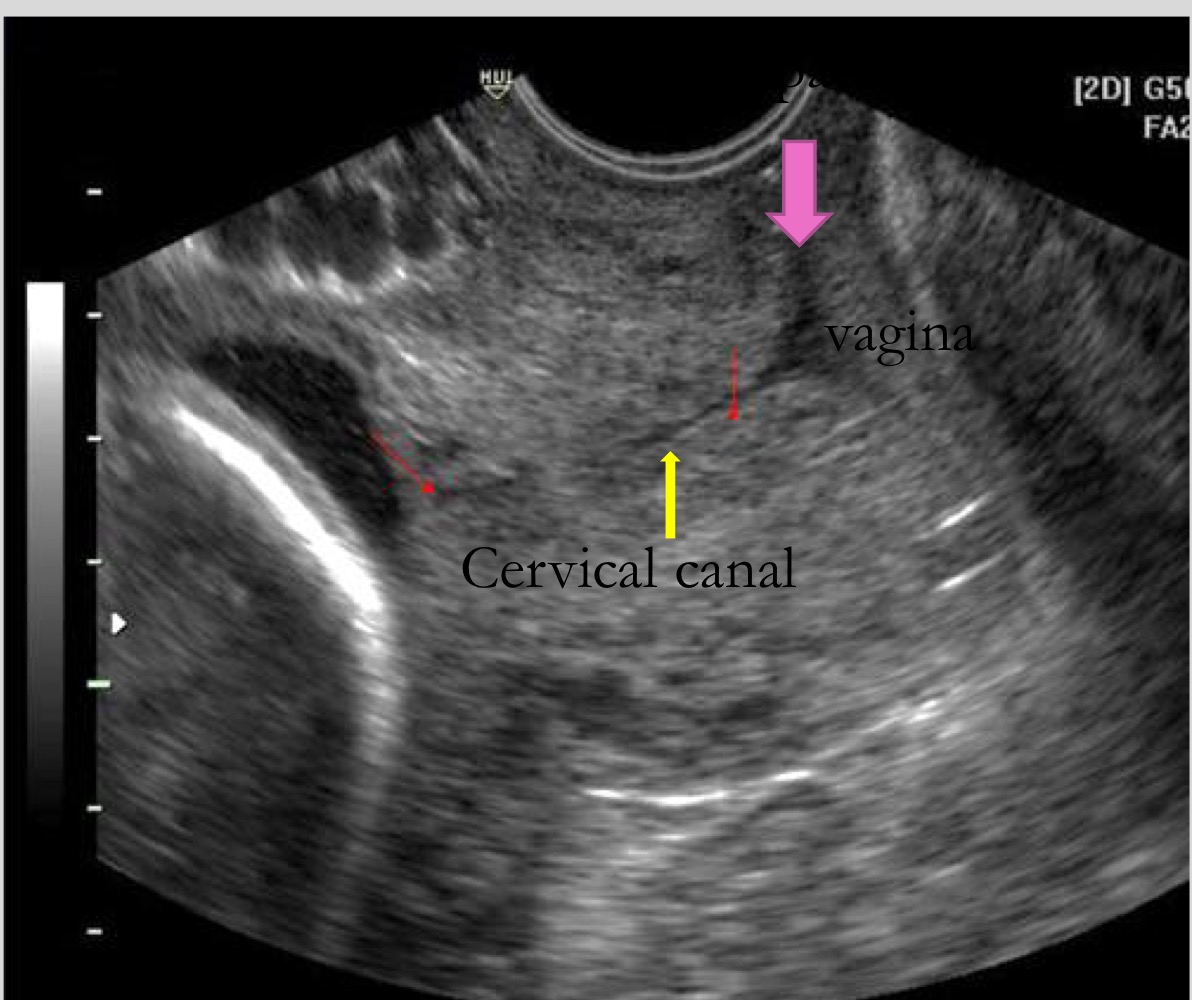

What structure is used as a guide when measuring cervical length

Cervical canal